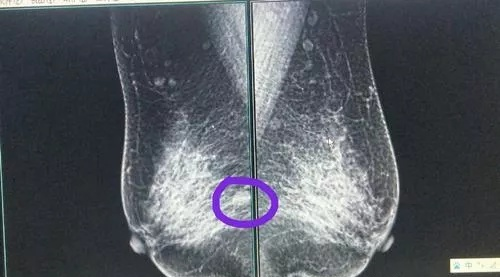

(2020年7月手术前的彩超)

当时也没太在意断断续续吃药吃了几个月,7月份去复查,增生和结节没有好转,当时都快崩溃了,医生说要是目前看的话只能是手术了。虽然我不想手术,但是医生说这如果后面发展到RADS 4a的话就有癌变的风险。没办法还是接受手术了。